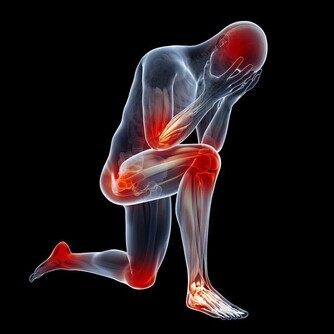

五忌:一忌久坐,久坐者傷肉。久坐易使肌肉逐漸衰退與萎縮。

二忌久立,久立者傷骨。老年人氣血運動全靠動靜結合調節平衡,久坐會影響血運,出現氣滯血凝致病。